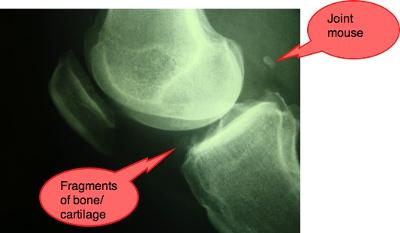

Joint mice